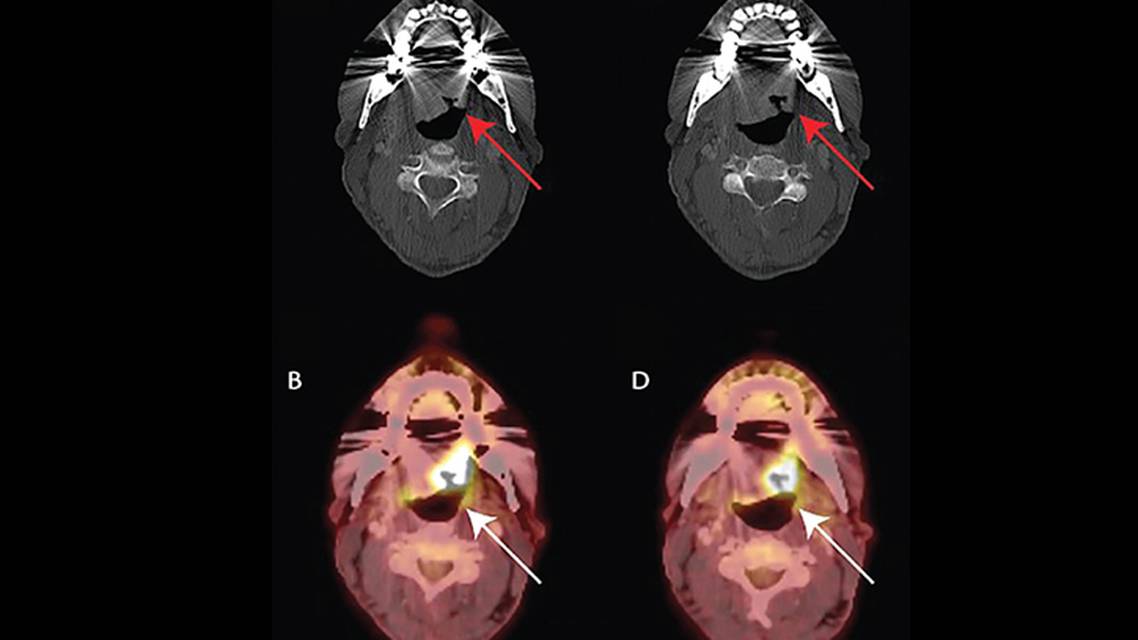

Figure 1. Consecutive slices of an axial CT (A, C) showing large ulceration in the left side of the base of the tongue (red arrows). PET imaging at corresponding slices (B, D) showing increased fluorodeoxyglucose (FDG) avidity within the ulceration (white arrows).

Subsequent consultation with a head and neck surgeon led to identification of a tumor at the base of the left side of the tongue that was not apparent on oral inspection. Contrast-enhanced axial CT scans of the neck showed a large ulceration in the left side of the base of the tongue extending towards the lateral oropharynx (Figure 1). Fluorodeoxyglucose-positron emission tomography (FDG-PET) revealed a hypermetabolic mass extending from the right of midline into the posterior base of the tongue on the left consistent with a tumor and a level 2A hypermetabolic lymph node, 1.5 cm in diameter, suggestive of metastatic disease (Figure 2).11